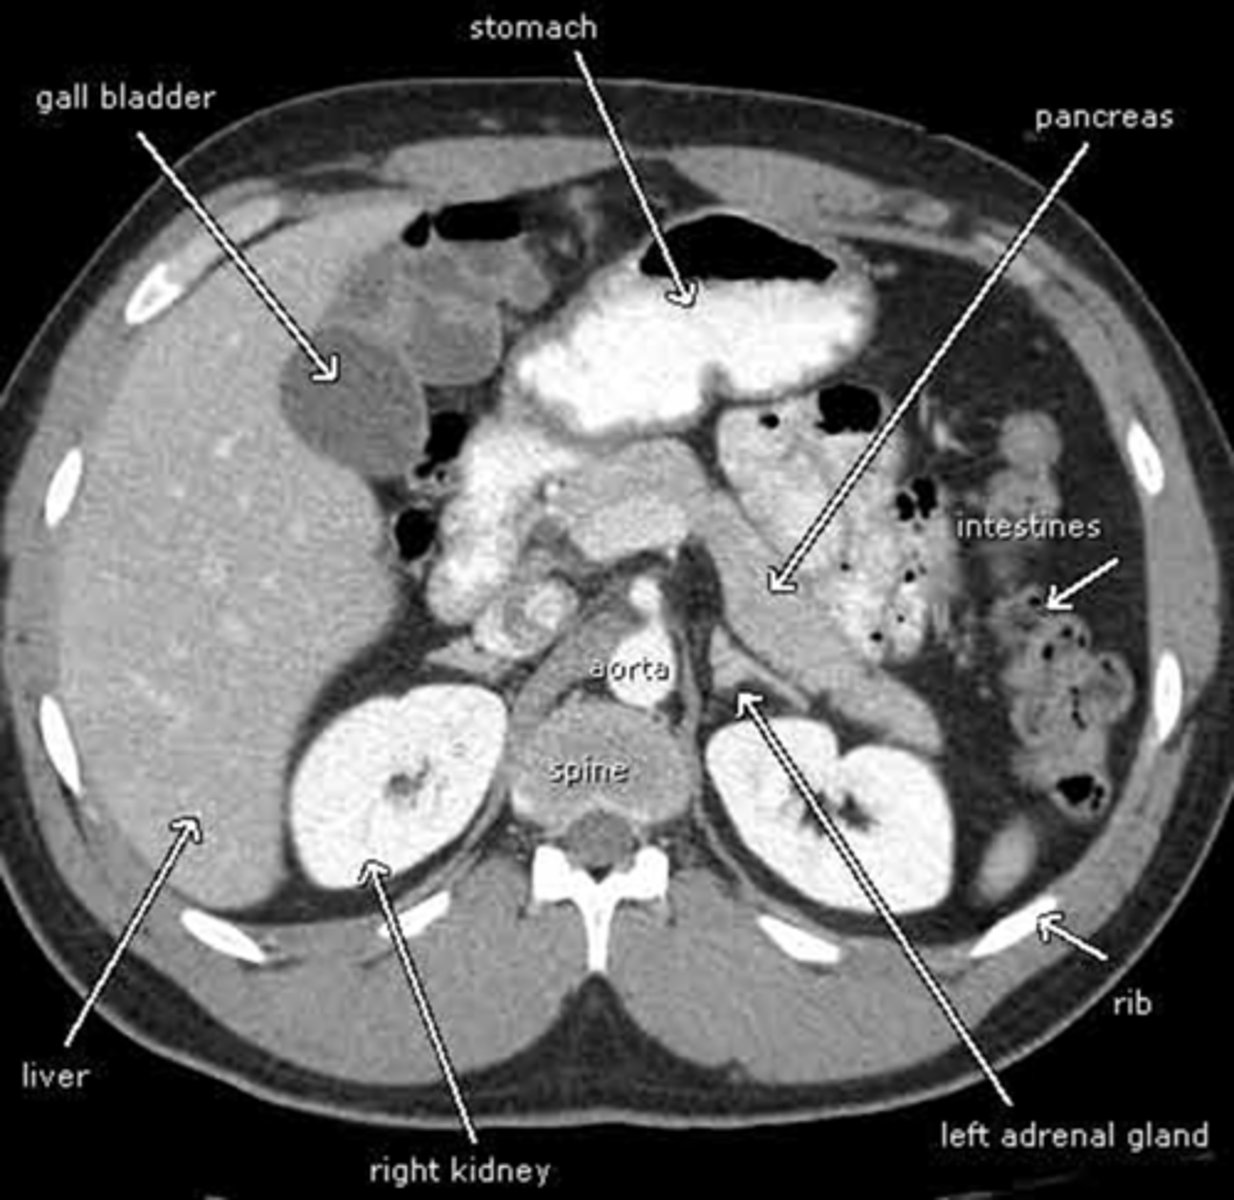

abdominal CT